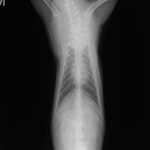

診断:胸部レントゲン検査にて、前縦隔領域に不透過性亢進領域を確認しエコー検査にてFNAを実施。細胞診の結果「低〜中分化型リンパ腫」と診断

前胸部にみられた不透過性領域の退縮が認められます